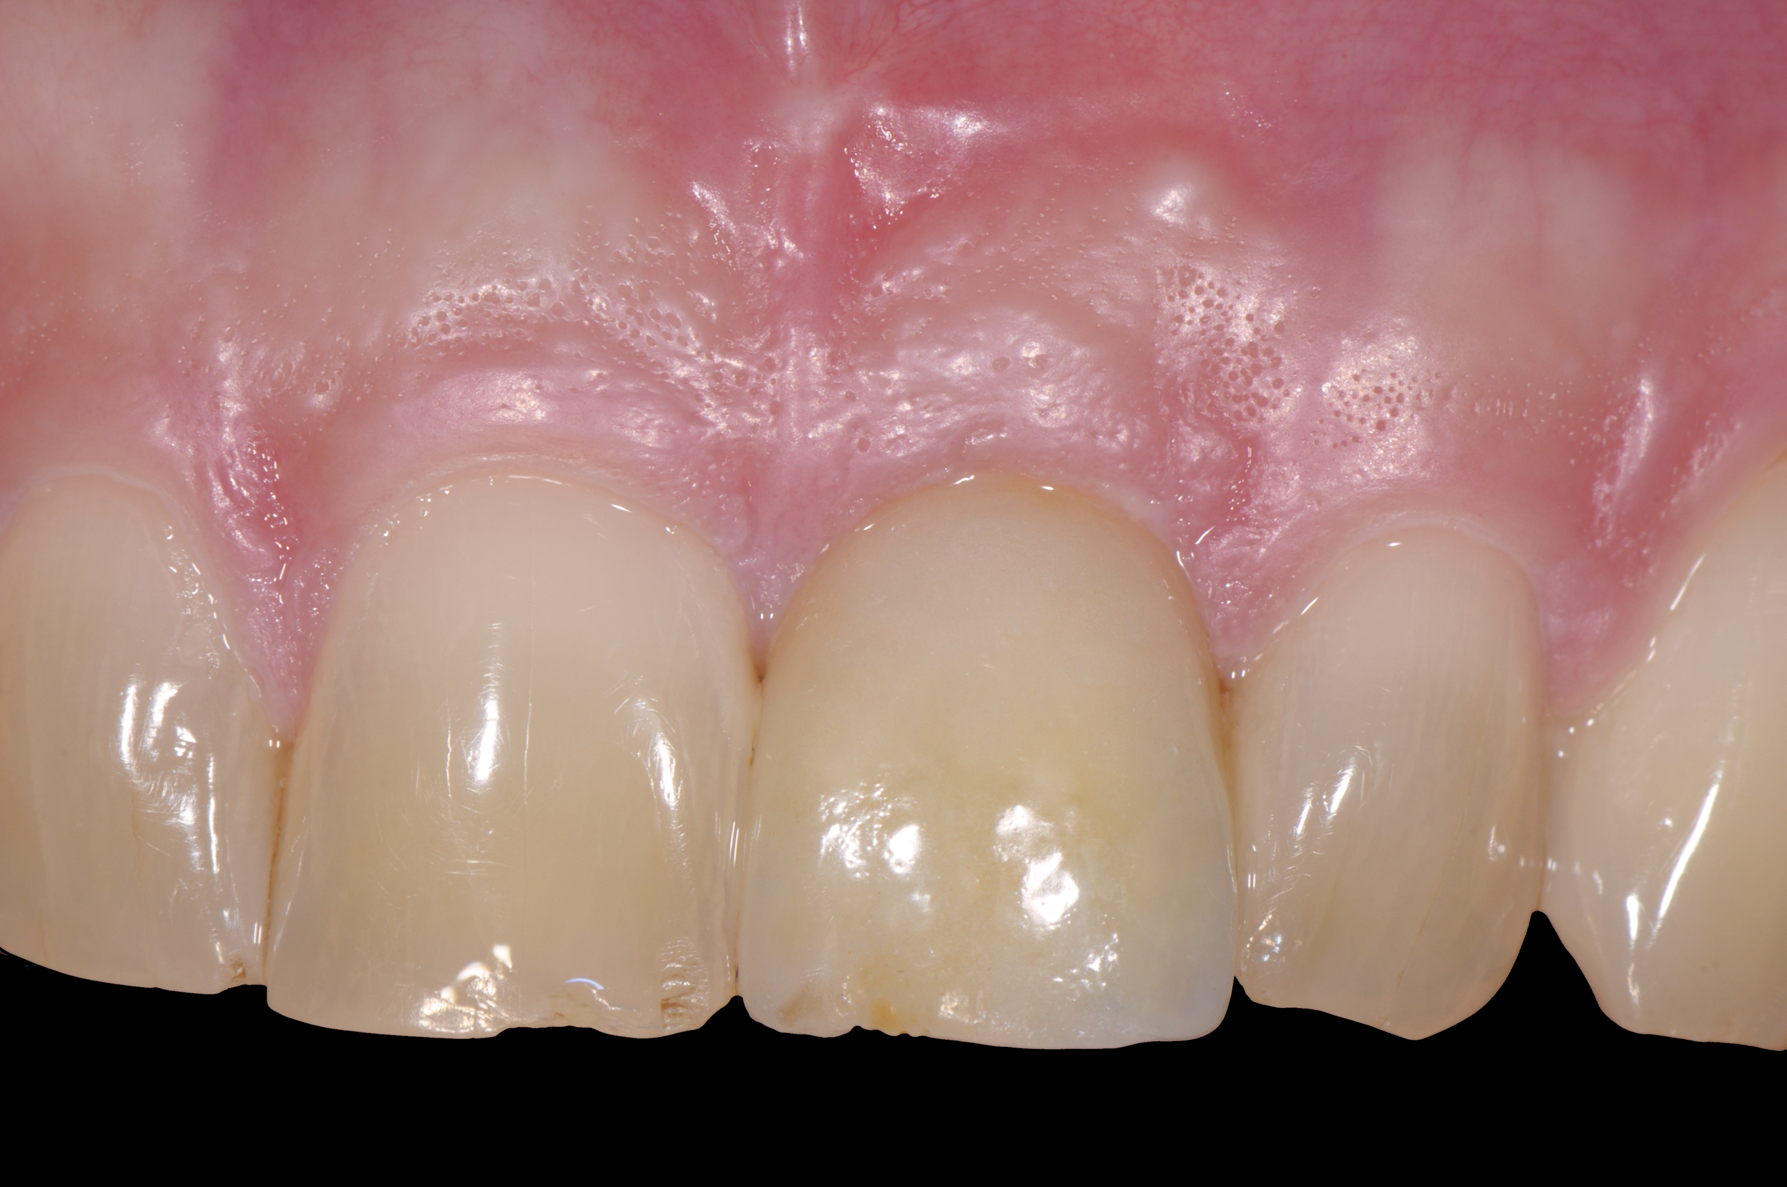

While more scientific evidence showing a lower tendency toward peri-implantitis may still need to be provided for ceramic implants, the essential argument for these implants based on clinical experience is the excellent and almost consistently inflammation-free peri-implant soft-tissue condition (Figure 3).

Fig 3. Soft tissue with zirconia implant free of inflammation.

Figure 3

Fig 12. Metal-free, removable, screw-retained restoration. Peri-implant mucosa had no inflammation or discoloration.

Figure 12